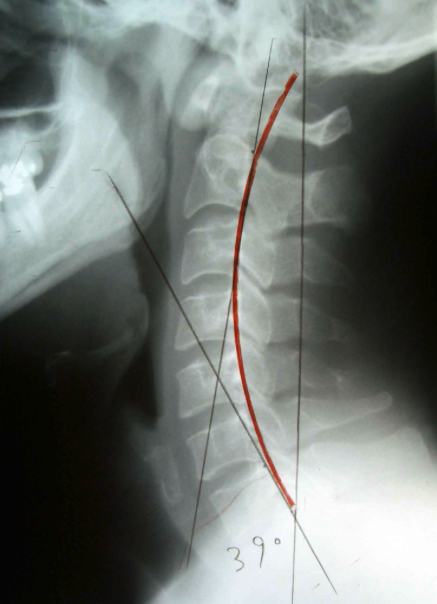

The alignment of the ZAJ surfaces is crucial for determining how rotation and lateral flexion are conductedThe joint surfaces are large and flat and are aligned at an average angle of 45° anteriorly and superiorly toward the end plate ( Fig. 1 2.9; Dvorak, 2008). Penning (2000,p. 89) reported a large variation in angles.

- 구상돌기관절면의 정열은 경추가 어떻게 회전, 측굴을 하는가를 위해 중요함. 구상돌기 관절면은 크고, 편평하겨 평균각도는 앞, 위로 45도임.